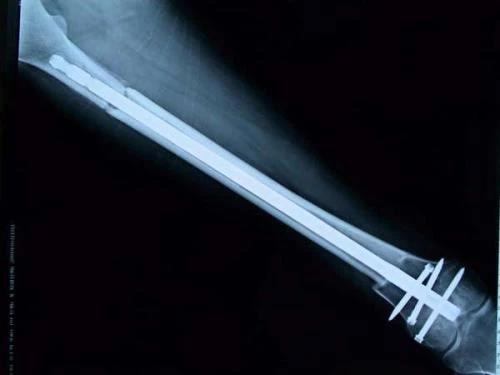

保肢治療指經(jīng)典型骨肉瘤在多學(xué)科團(tuán)隊醫(yī)生共同努力下完成的新輔助化療、保肢手術(shù)和輔助化療等一系列治療總稱,其目的是在提高患者生存率的前提下,減少局部復(fù)發(fā)、盡量保留良好的肢體功能。肢體經(jīng)典型骨肉瘤保肢治療方法如下圖所示:

新輔助化療的目的是盡早殺滅遠(yuǎn)處微小轉(zhuǎn)移灶,縮小腫瘤及周圍炎性水腫反應(yīng)區(qū),以利于后續(xù)的保肢手術(shù);觀察腫瘤對化療的敏感性,為進(jìn)一步指定個體化的術(shù)后化療方案奠定基礎(chǔ)。骨肉瘤新輔助化療下的保肢治療如下圖所示: